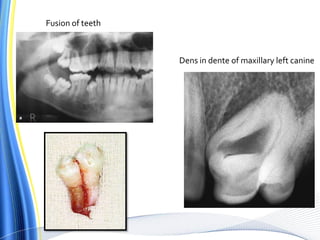

5. Geminated / dilacerated tooth

Dens in dente of maxillary left canine

Fusion of teeth